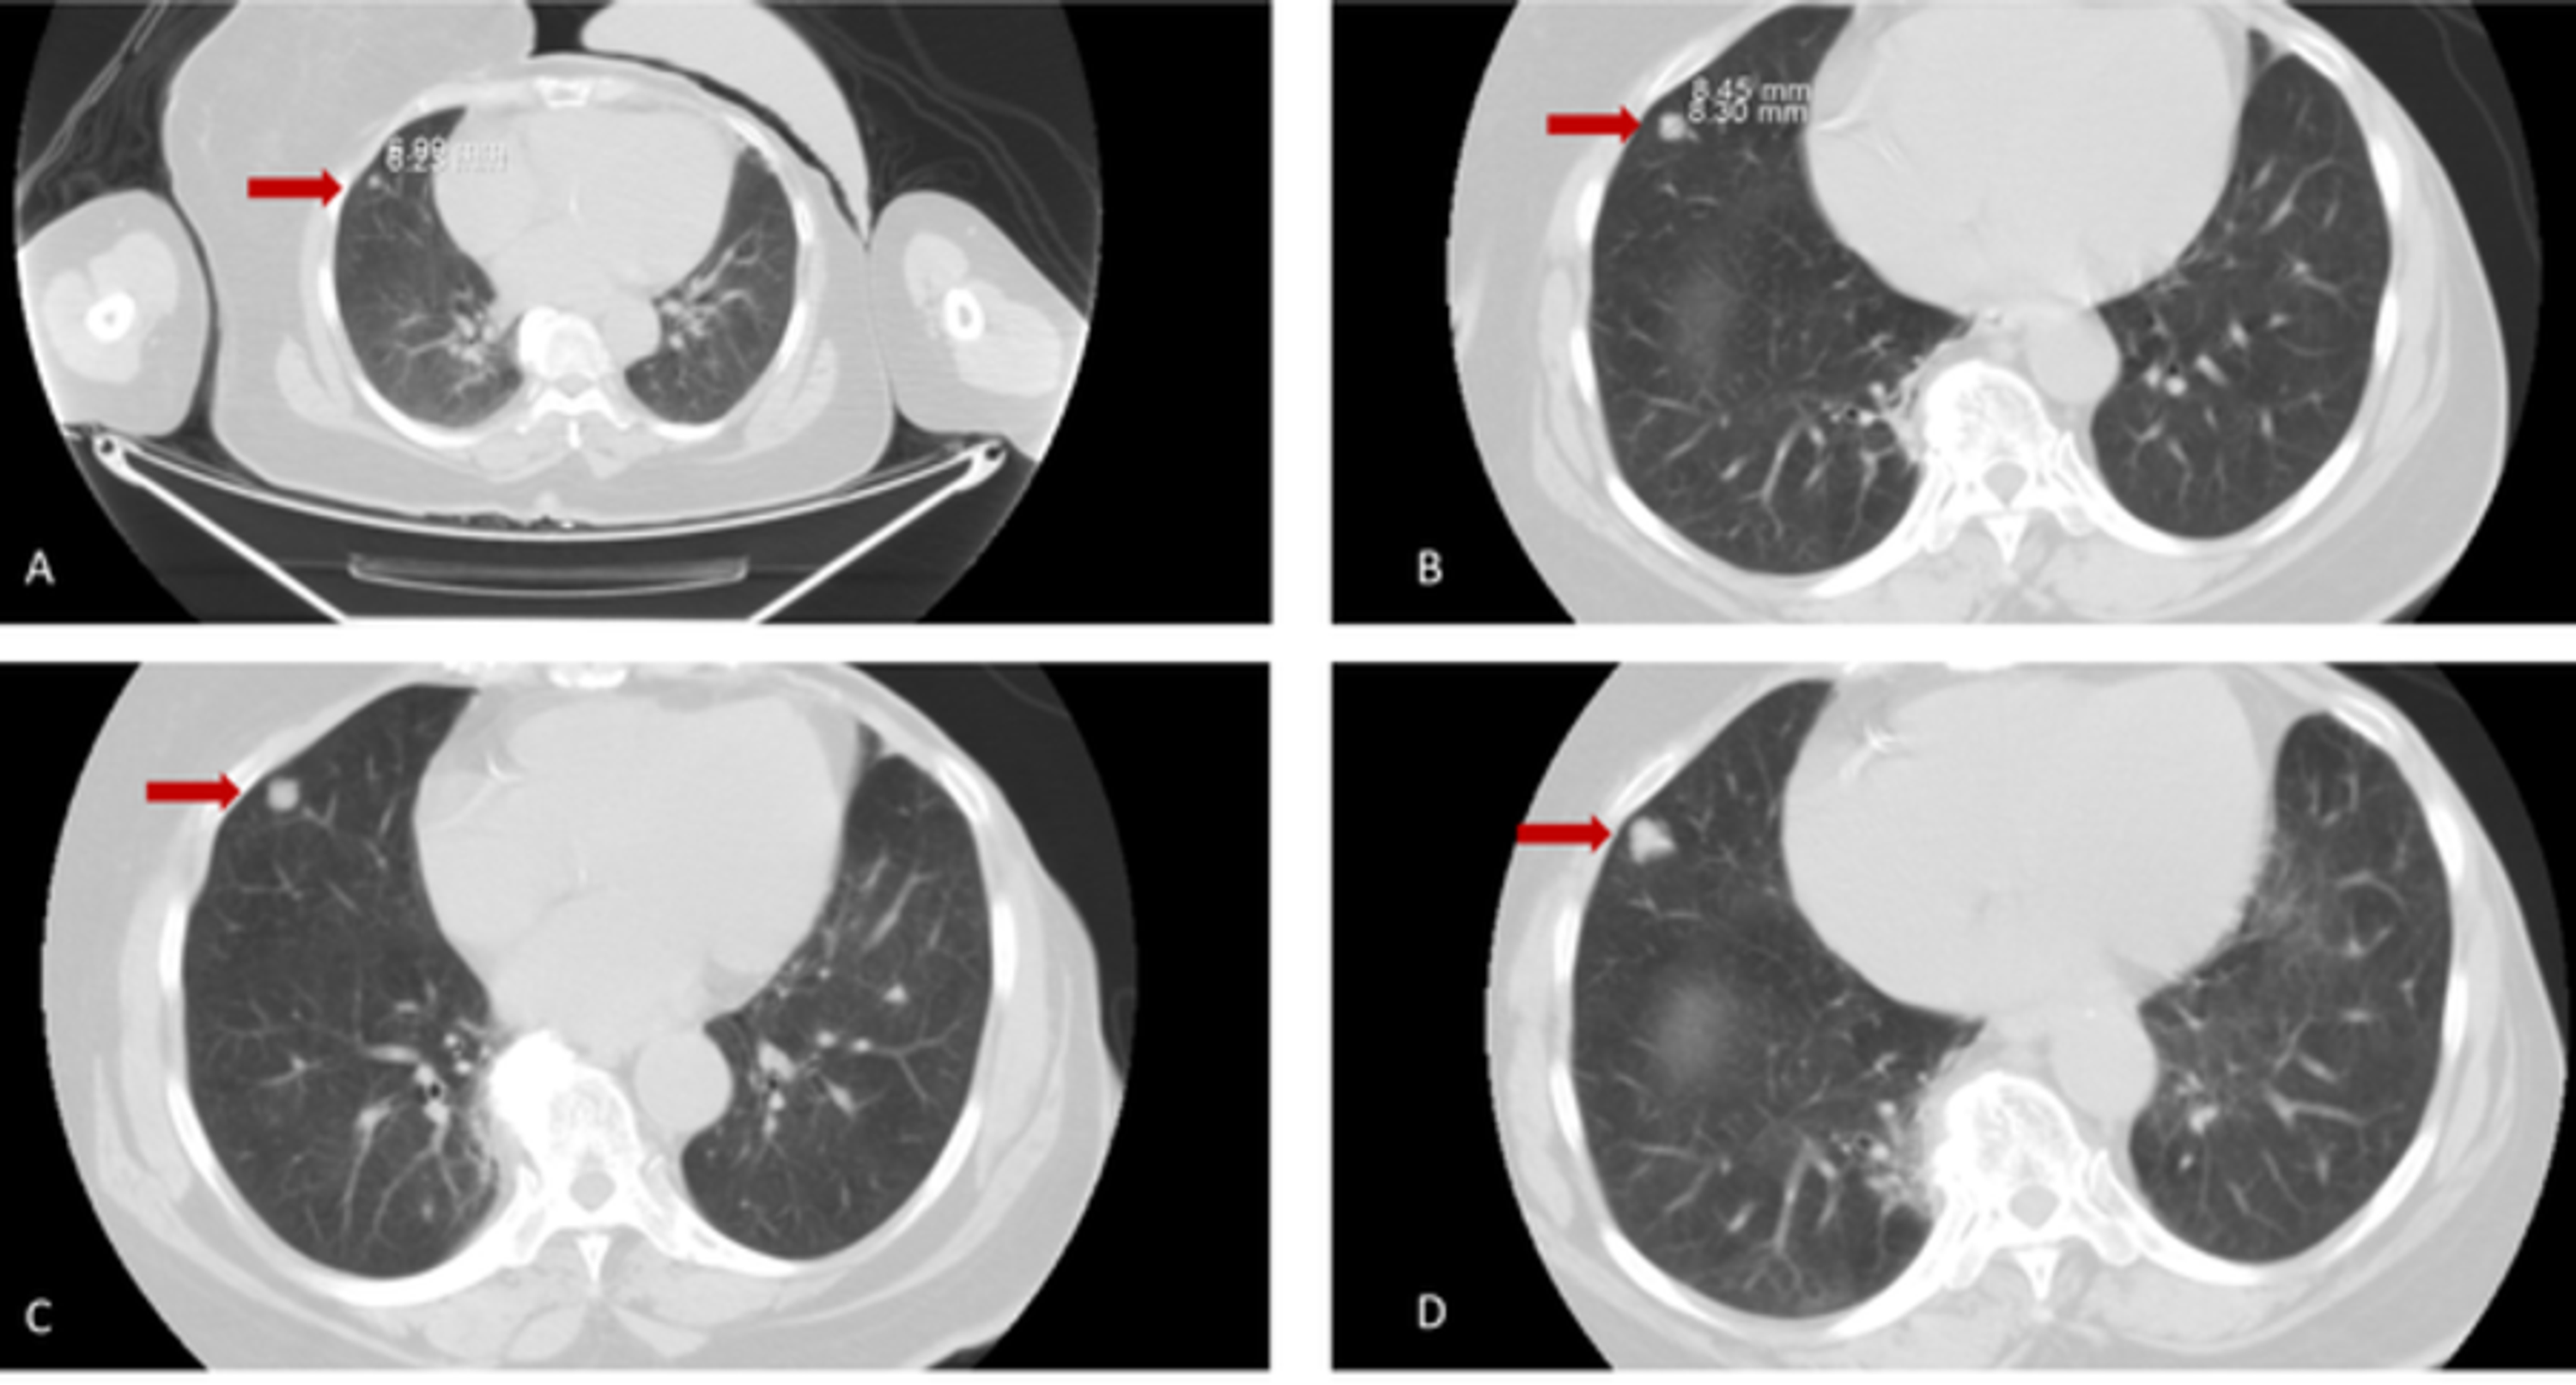

Chest CT (Multiple spindle cell hemangiomas in both lungs) Download Spindle Cells In Lung Spindle cell lung cancer (spcc) is a rare type of nsclc which portends a poor prognosis. Spindle cell carcinoma is an aggressive (rapidly developing) malignancy that has elements of both carcinoma and sarcoma. Spindle cell carcinoma is a rare pulmonary malignancy. This type of tumor shows concurrent. For a correct differential diagnosis, immunohistochemical and molecular techniques are indispensable. Here we. Spindle Cells In Lung.